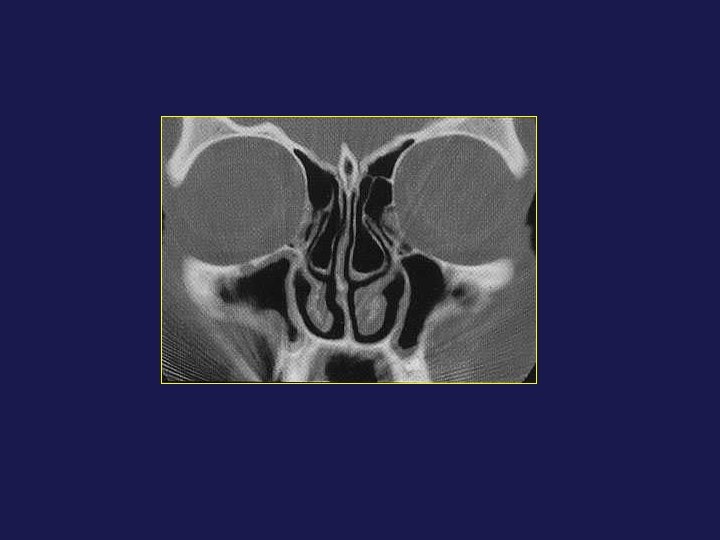

RADIO-ANATOMIE TDM DES CAVITES NASOSINUSIENNES E. Menif Service d’Imagerie Médicale Hôpital la Rabta Tunis

RADIO-ANATOMIE TDM DES CAVITES NASOSINUSIENNES E. Menif Service d’Imagerie Médicale Hôpital la Rabta Tunis - Tunisie MASTERE DE NEURORADIOLOGIE Sousse 2008